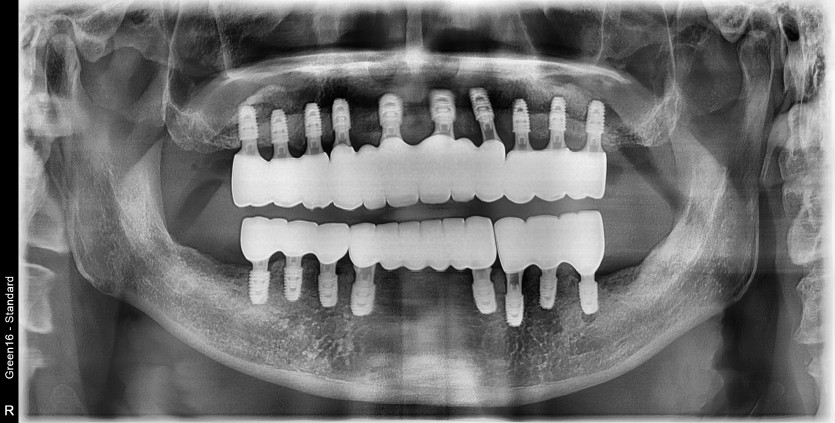

만 56세 전체 임플란트 증례

전체 임플란트 증례입니다.

18개의 임플란트로 완성하였습니다.